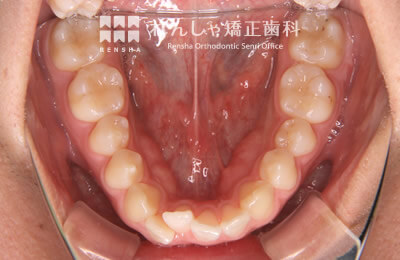

成人

歯列のサイズや形態を大きく変更することができませんが、歯列が極端に狭くなっている場合や、奥歯が前方に移動し前歯ががたついているケースでは、歯列の拡大や奥歯の後方移動を行うことで永久歯を抜歯せずにがたつきを改善できることがあります。このような場合はアライナー型(カスタムメイド)矯正(歯科)装置も治療の選択肢として有効です。

治療前

治療中

治療後

| 主訴 | 前歯のがたつき |

|---|---|

| 診断名 | Angle Class I 叢生 |

| 初診時年齢 | 18歳8か月 |

| 装置名 | マウスピース型カスタムメイド矯正歯科装置(製品名インビザライン・完成物薬機法対象外) |

| 抜歯非抜歯 | 非抜歯 |

| 治療期間 | 1年2か月 |

| 費用の目安 | 約55万円+消費税(検査料金、都度の処置費用等も合わせた総額) |

| リスク副作用 | 歯の移動に伴う軽微な歯根吸収、歯槽骨吸収、歯肉退縮(いずれも本症例ではほぼ無し)、矯正器具装着中のカリエスリスク増大(本症例ではカリエス発生無し) |